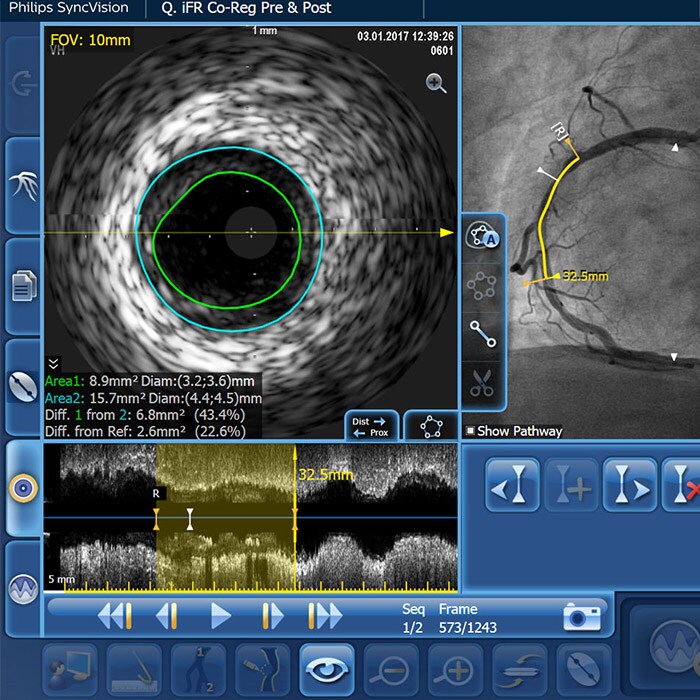

IVUS-guided vs. angiography-guided outcomes3